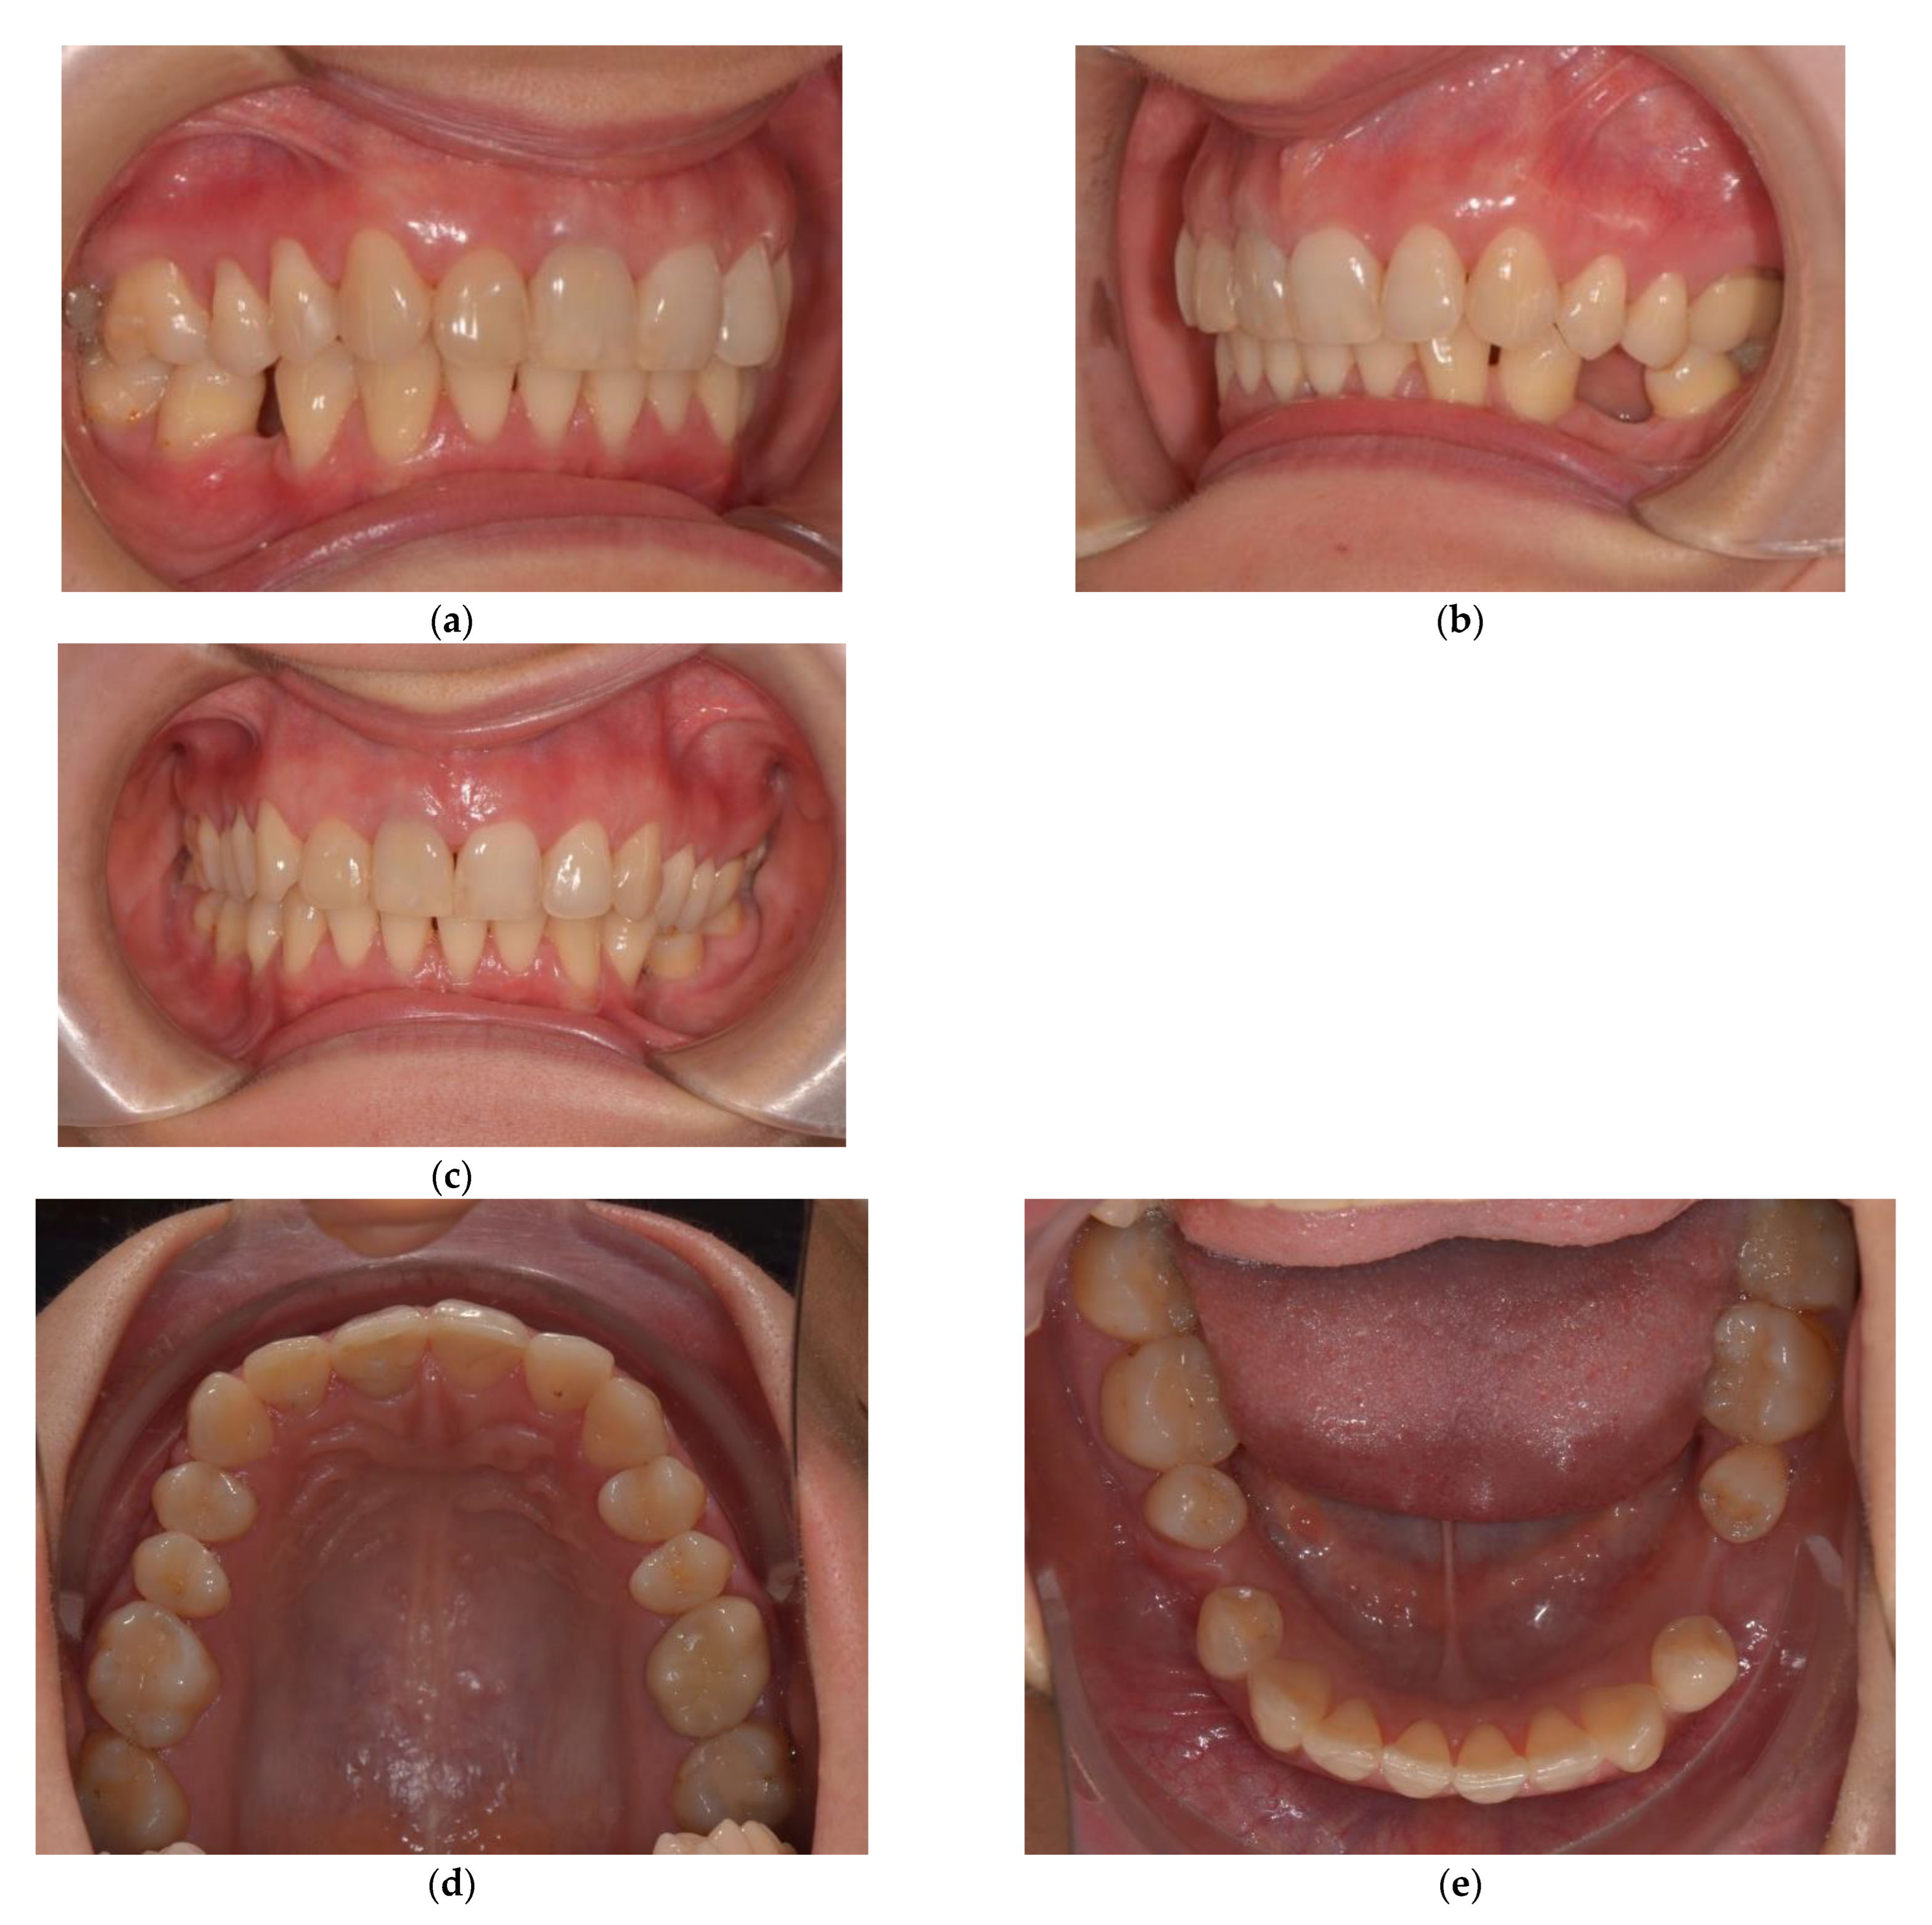

A 28-year-old woman, seeking replacement of missing lower first molars, with second mandibular premolars shifted distally and rotated to the edentulous space, came to our practice. Prosthetic treatment of the edentulous spaces was limited by overeruption of upper first molars and premolars, as well as by the rotated teeth. The occlusal plane was irregular, with extrusion of the upper first molars and premolars into the edentulous spaces and a lower midline shift of 2 mm towards the right side (Figure 2). She had a hypodivergent skeletal pattern, a class II skeletal pattern with a small anterior facial height, skeletal deep bite tendency, and increased overbite and overjet (Table 3).

Figure 2.

Initial situation (a) Right lateral occlusal view; (b) Left lateral occlusal view; Initial situation (c) Frontal occlusal view; Initial situation (d) Upper arch; (e) Lower arch; Initial situation, extraoral photos (f) Frontal view; (g) Lateral view.

The main aim of the treatment objectives, namely the intrusion of the upper posterior teeth, has been achieved. The orthodontic treatment is ongoing in order to solve additional objectives, such as midline correction and space distribution for prosthetic treatment (Figure 8).

Figure 8.

Post-intrusion intraoral photographs (a,b) Left lateral occlusal view; (c) Frontal occlusal view; (d) Upper arch; (e) Lower arch; Post-intrusion intraoral extraoral photos (f) Frontal view; (g) Lateral view.